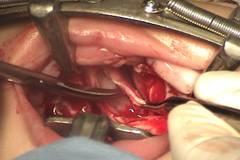

3. Como se trata de una hendidura amplia no se puede pretender hacer una z-plastia de la mucosa nasal, por lo cual se debe cortar junto con la inserción anómala de los músculos del paladar. De esa manera el paladar se va hacia atrás. (Fig. 5 y 6).

Figuras 5 y 6: Momento en que se está cortando la mucosa nasal y el músculo a nivel de su unión con el paladar duro. De esa manera sí se alarga el paladar.